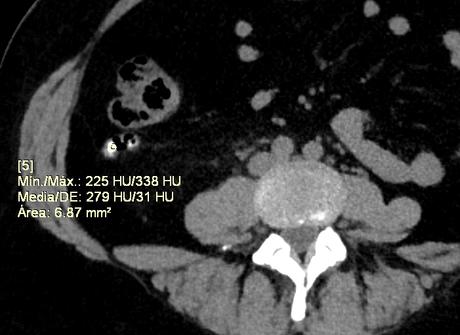

Se realiza búsqueda intencionada de la región de fosa iliaca derecha, apreciando una imagen tubular, en fondo de saco de ciego y presenta estriación de la grasa periapendicular la cual mide 10 mm en sentido anteroposterior, con presencia de un apendiculito en su interior de 5 mm, con densidad de 279 UH.